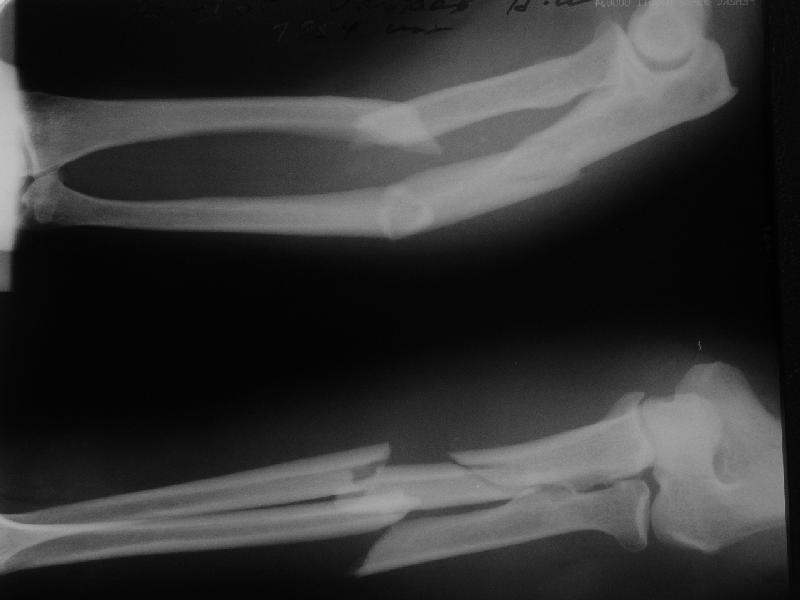

В приложении заключительный момент операции и итоговые снимки. Сделали закрыто. Оба гвоздя (ChM) заперты динамически не только из-за лени ;-) но и

потому, что форма линий излома такова, что и упор будет, и ротационной подвижности на месте переломов не ожидается. Комментарии и критика приветствуются.

The reductions are nice, but I'd be concerned that the fracture of the radius will move with pronation & supination encouraging nonunion (since the nail is essentially fixed to the distal radial shaft and free to move with respect to the proximal radius.

I'd lean toward 4-5 weeks in a long arm cast, giving him "credit" for the past week or so of immobilization.

The reduction is excellent but I am not sure that you have rotational stability of the proximal radial fragment (no proximal locking) this could rotate with pronation and supination. If you are planning to cast then ORIF with plates is superior because casting is not necessary. I would expect these fractures to heal with callus as opposed to primary bone healing seen with plated fixation. Is healing with callus in the forearm a problem? I am not sure I know. How do these rods and locking screws compare price wise with plate and screw fixation (more expensive I would expect)? How often is hardware removal required? What was your operative time? I think these are all factors to consider when comparing a new treatment method with an established one.

Long arm cast for 2 weeks then Active ROM would be my approach. Is the elbow OK ?? radial head looks a little posterior though???

Good technique, but in comminuted / segmental #s like this ,isn't it better to lock statically at both ends? I would be concerned about possible rotation.I dont have any experience with closed nailing of forearm though. Is he going to be in a cast for 6 weeks?

Length 200 and 240 mm, diameter 4 mm.

Yes, the radius. The set includes cannulated reamers 4 and 5 mm. Though finally our custom-made 5 mm hybrid of reamer and awl was used.

mb> can we accept this reduction and this fixation as anatomical and stable?

Axis, length, radial bowing and rotation are restored. Stability is relative as in any nailing, but enough for early function.